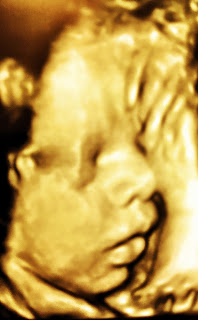

At this point, I had been to see my doctor every week starting at week 36. My appointments were actually at the week and 5 day mark every Wednesday. Each week they’d check the baby via ultrasound and check all of my vitals. By week 38/5days I was at the 28 pound mark and only just beginning to swell a little in my feet and calves, just the normal pregnancy stuff.  My usually low blood pressure was starting to creep up a bit and although higher than normal for me, not too high for medical concern. By week 39, I had gained 10 more pounds, seemingly overnight and my blood pressure was consistently in the 120’s/80’s which the doc said still wasn't out of the normal range. The weight gain surprised me as the normal is considered to be 1-2 pounds a week, not 10, but I wasn't yet concerned as I thought this was all part of a normal pregnancy!  I was alternately happy to finally have a bigger belly because people kept saying mine looked too small for how far along I was in the pregnancy which was making me paranoid that my baby wasn’t growing well even though the weekly ultrasounds kept showing me that this was a big baby. *Note to pregnant or soon to be pregnant women. All science says that the mother's belly size has nothing to do with size of the baby. This is especially true when you’re over 6 feet tall (1.8m) My boy, Aidan just had much more room to stretch out in. He was comfy in there. In fact, he was too comfy…

So, on Wednesday September 7th at 2pm, they did my ultrasound and baby Aidan looked great. They did the Fetal Monitoring and his heart sounded great and even vivacious! The name Aidan means “Little Fire” and my little fire was thriving in me. Next stop was to see the doc and discuss a plan and this is when my best laid plans went to serious hell…